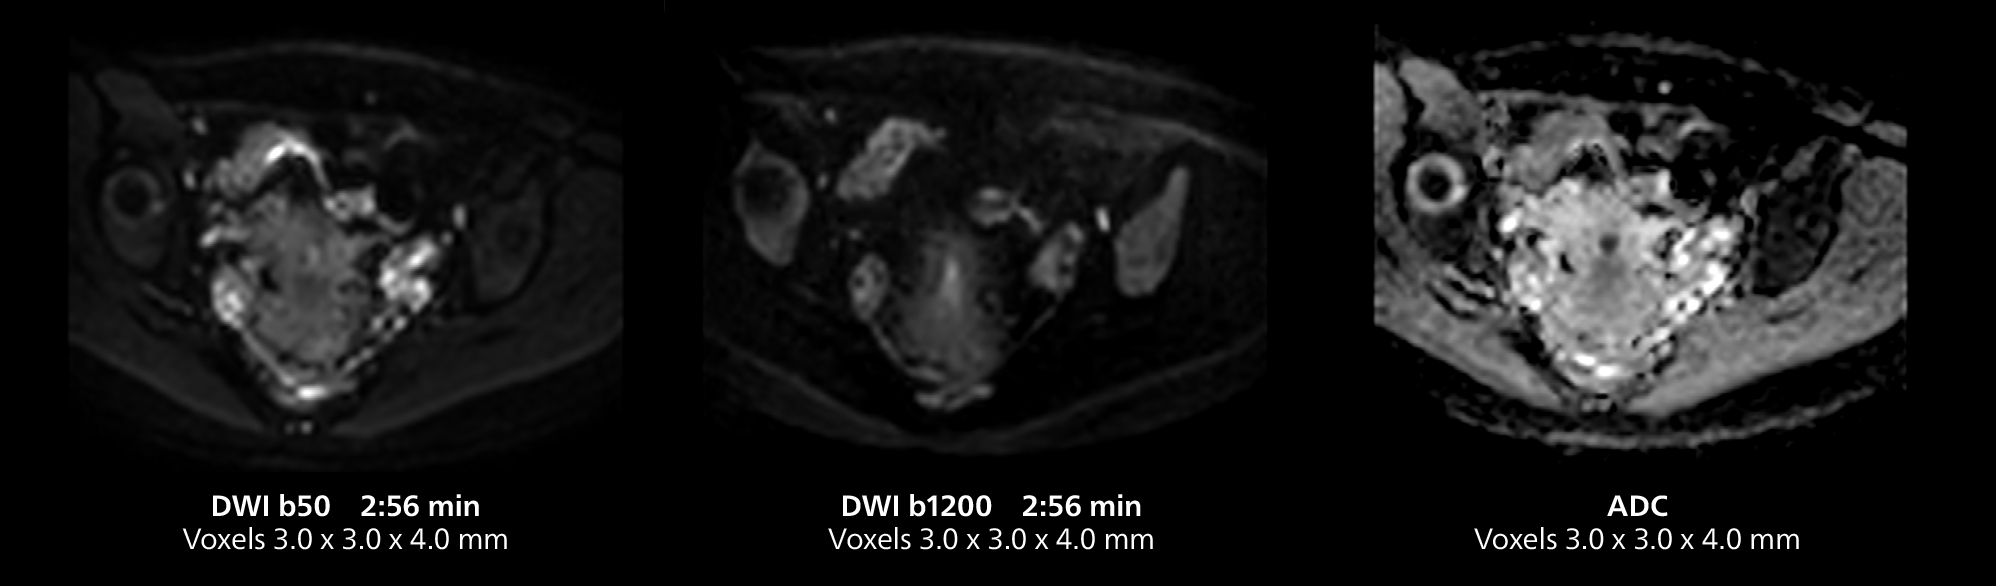

This case includes 3D free breathing and 4D dynamic free breathing MRI of a metastasized liver. A high quality fatsat sequence with good resolution is obtained in 1:36 minutes with T2-weighted MultiVane XD.

Dr. Gellée highlights the robust free-breathing scans as “the feature that makes the biggest difference in my daily work. The 3D free breathing sequences are very reproducible, and the axial acquisition is very good. For example, in endometriosis, which is one of my focus areas, it provides high contrast and good resolution so that I can see small details. We also use free breathing for liver and pancreas imaging. In multi-phase liver studies, 4D Free Breathing delivers 3-second temporal resolution, making a dynamic scan with more than one arterial phase possible.”

She also uses free breathing with 3D mDIXON to obtain in-phase, water and fat images in a single scan. “It is very reproducible before and after gadolinium, which makes it useful for liver imaging,” she adds.